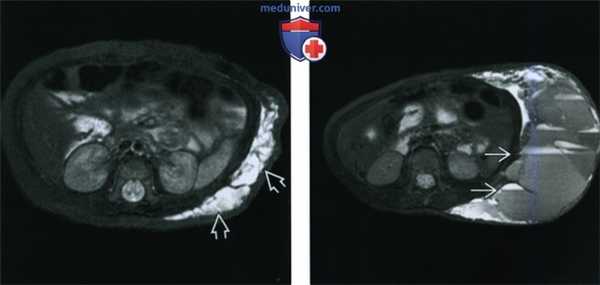

(Слева) При аксиальной МРТ Т2 FS у ребенка с новообразованием бокового отдела живота визуализируется объемное образование с интенсивностью сигнала, соответствующей жидкости, вытянутой формы, разделенное перегородками, - типичная лимфатическая мальформация.

(Справа) При аксиальной MPT T2 FS у этого же пациента месяц спустя определяется выраженное перемежающееся накопление контраста в образовании. Визуализируются многочисленные уровни «жидкость-жидкость», типичные для продуктов лизиса крови, обусловленных внутренним кровоизлиянием.